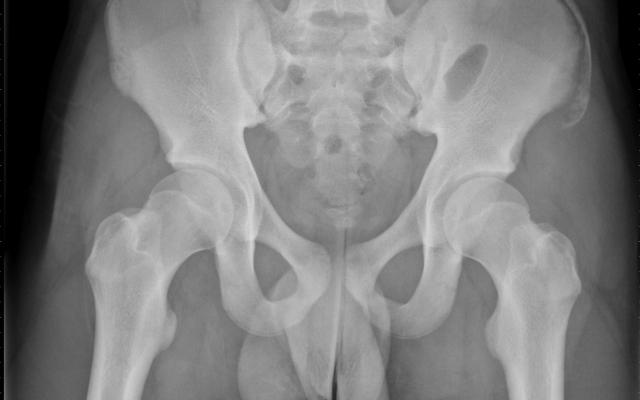

Een 15-jarige jongen werd op de afdeling Eerste Hulp gezien wegens pijnklachten aan zijn linker heup na een ongeval op het voetbalveld. Het traumamechanisme bestond uit het trappen met het rechter been in de grond, waarbij het linker been bleef staan en het bovenlichaam naar voren roteerde. Bij functieonderzoek was er een verminderd vermogen het linker been actief te strekken ten opzichte van het rechter been. Een anteroposterieure röntgenopname van het bekken toonde een avulsiefractuur van de linker crista iliaca, ter hoogte van de spina iliaca anterior superior (figuur). Deze fractuur is zeldzaam en ziet men met name bij…